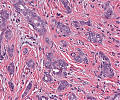

Leiomyom

Randliche Anteile des Leiomyoms mit verdrängendem Wachstum gegenüber dem Myometrium